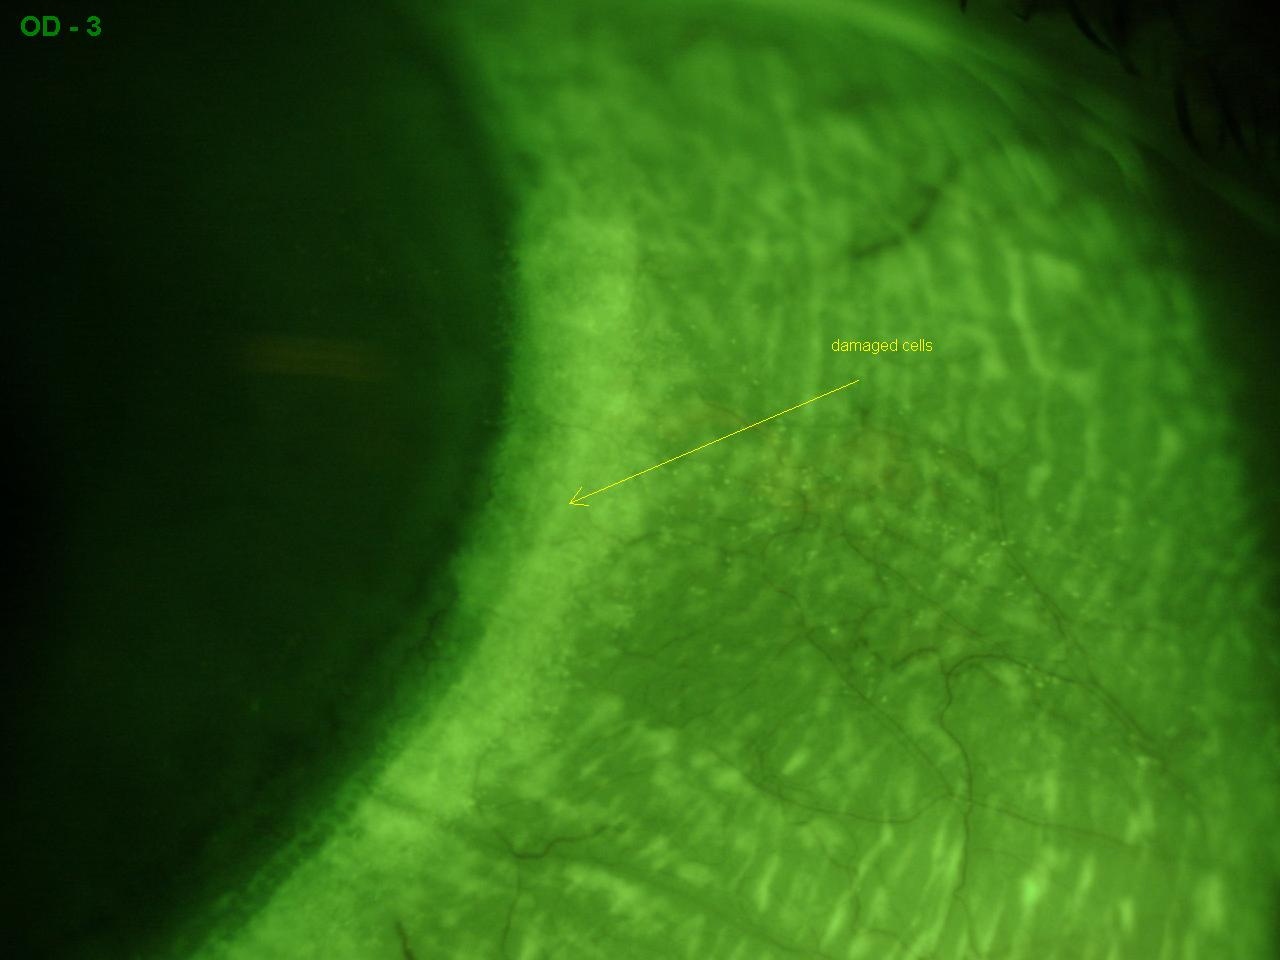

Can Contacts Damage Your Eyes 2023. Other eye drops may contain preservatives and other types of chemicals that can irritate the eye and damage contacts, says Dr. Assess the Extent of the Damage. Contact lenses are by far more convenient than wearing glasses. The eye damage can be temporary or permanent and can take a few hours to a few days to realize the damage has occurred. Contacts are designed to cover the cornea of the eye. Can Contacts Damage Your Eyes 2023.